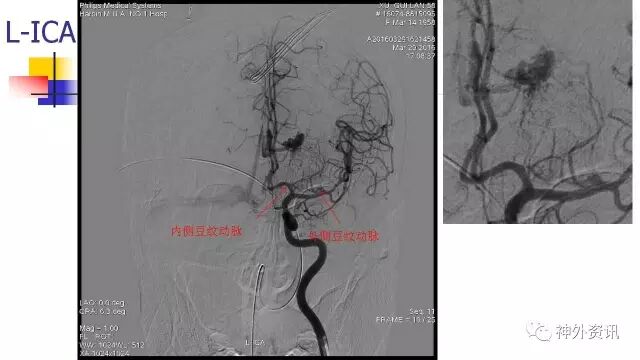

斜位动态